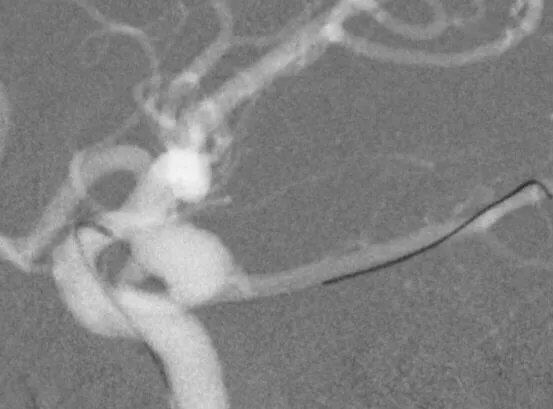

左侧后交通动脉瘤,胚胎型大脑后动脉

3D

局部观,宽颈,涉及颈内动脉和后交通动脉

椎动脉造影见左侧大脑后动脉P1段很细

栓塞的关键是既要保持颈内动脉通畅,又要保持后交通动脉通畅。双导管单纯填塞;通过颈内动脉释放支架灯笼技术辅助是可选的方案。本例是通过后交通动脉释放支架,利用支架摆尾技术(half-T)来进行栓塞。支架导管塑型